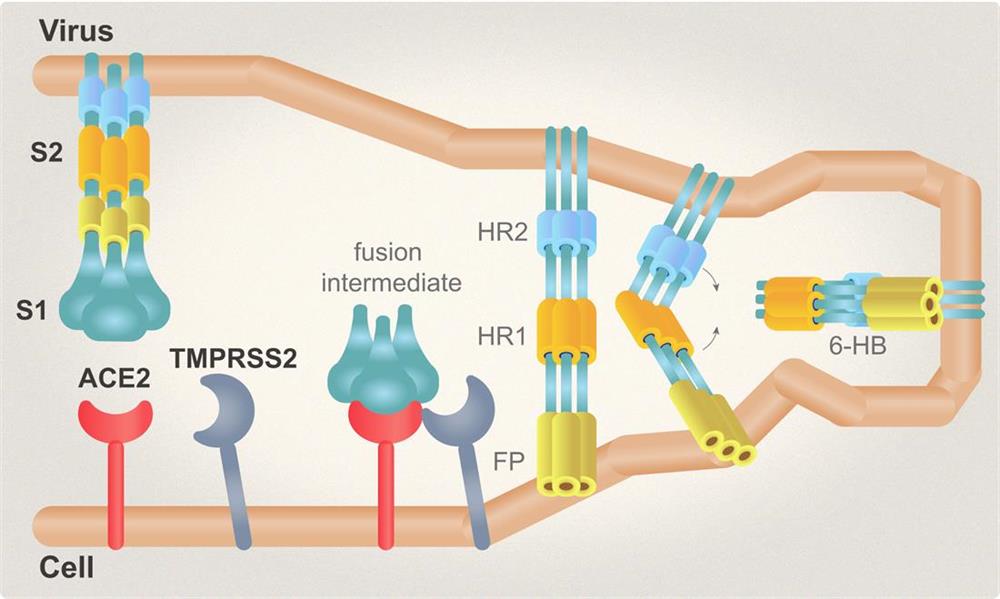

| Spike (S) | Spike full-length (~1273 a.a. in SARS-CoV-2) protein precursor is cleaved into glycosylated subunits, S1 and S2 (S2’). S1 binds to the host’s receptor, ACE2, while S2 mediates viral and host membrane fusion. | 1 |